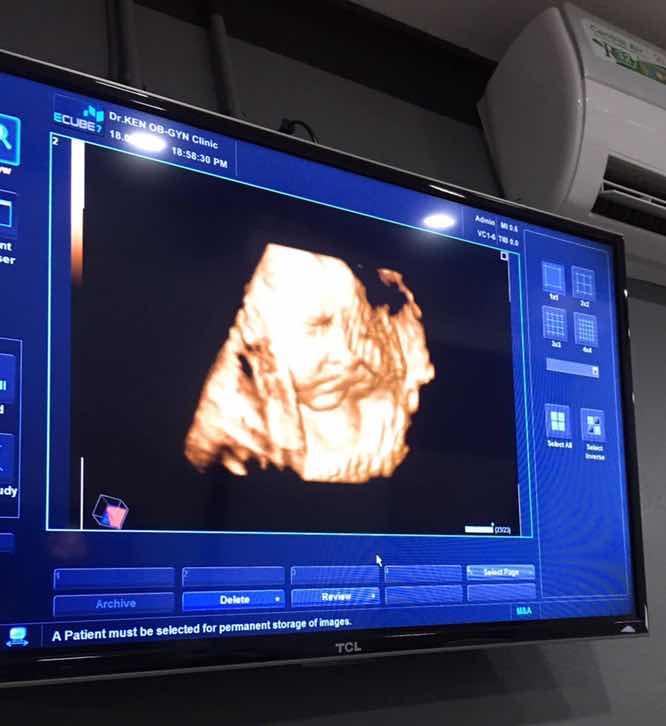

อัลตร้าซาวด์

ตอนนี้ตั้งครรภ์ได้ 36 สัปดาห์ 6 วัน แล้วค่ะ คือไปหาหมอและซาวด์ดูน้องทุกเดือน น้องจะปิดหน้าตลอดถ้าไม่เอามือบังก็คว่ำหน้าลง แต่วันนี้ดีใจมากได้เห็นหน้าน้องครึ่งนึงอีกครึ่งรกบัง แต่ก็ทำให้เราตื่นเต้นมาก รอเจอน้องไม่ไหวแล้ว ? มีคุณแม่ที่ยังไม่เห็นหน้าน้องเหมือนเรามั้ยคะ?